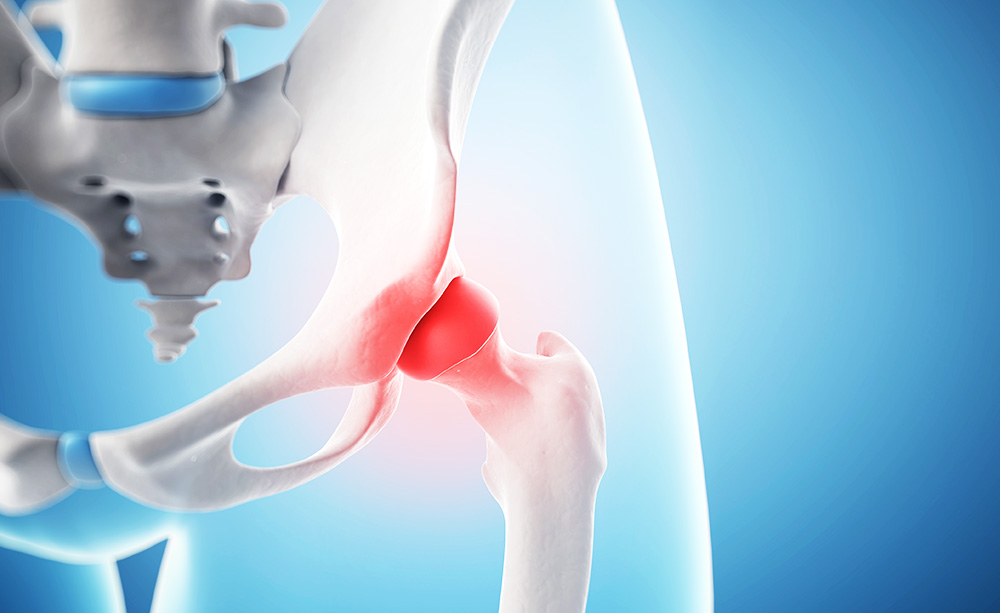

탁구공 모양의 정상 고관절에 비해 대퇴골두 무혈성 괴사의 고관절은 찌그러져보인데요. 뼈가 건강하려면 산소와 영양 공급이 충분해야 하는데 이 역할을 하는 것이 혈액인데요.

혈액 공급이 원할하지 않으면 대퇴골두에 괴사가 일어나요. 대퇴골두 무혈성 괴사의 원인은 정확하게 밝혀지지 않았지만 과음, 과도한 스테로이드제 복용이 혈액 점도를 높여 발생하 다고 알려져 있어요. 주로 30~50대에 발병한다고 해요.

대퇴골두 무혈성 괴사의 초기 증상은 고관절 통증인데요. 괴사된 대퇴골두가 납작하게 찌그러지며 보행이 불가능해지고 다리 길이가 짧아져요.